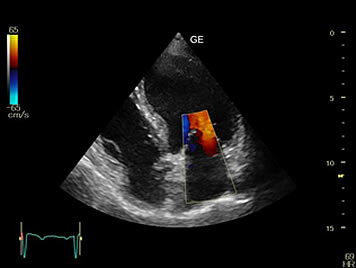

Ultrasound scan is used to detect whether the prostate is enlarged or not and to detect disorders within the prostate and abnormal growth within it including those from non cancerous enlargement of the prostate and from prostate cancer.